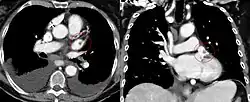

CT scan of the chest showing a thrombus in the left atrial appendage (left: axial plane, right: coronal plane)

In patients with atrial fibrillation, mitral valve disease, and other conditions, blood clots have a tendency to form in the left atrial appendage.[12] The clots may dislodge (forming emboli), which may lead to ischemic damage to the brain, kidneys, or other organs supplied by the systemic circulation.[29]

In those with uncontrollable atrial fibrillation, left atrial appendage occlusion may be performed at the time of any open-heart surgery to prevent future clot formation within the appendage.[30]